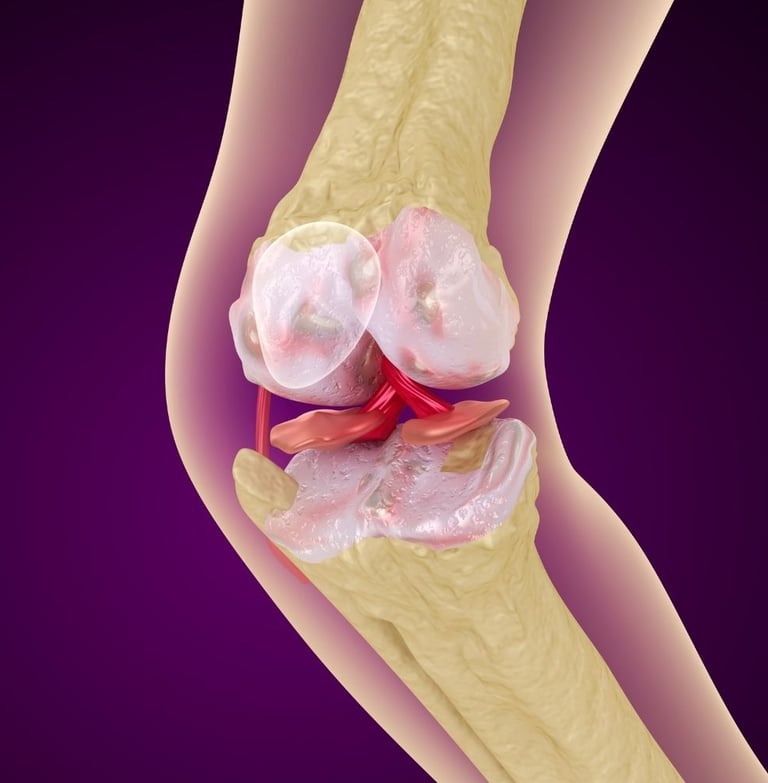

Diz kireçlenmesi, tıbbi adıyla osteoartrit, özellikle 50 yaş üstü bireylerde hareket kısıtlılığının ve kronik ağrının en büyük nedenlerinden biridir. Dizdeki kıkırdak dokusunun zamanla aşınmasıyla ortaya çıkan bu durum, "yaşlılık hastalığı" olarak bilinse de günümüzde yanlış beslenme ve hareketsizlik nedeniyle daha erken yaşlarda da görülmektedir.

Peki, her diz kireçlenmesi mutlaka protez ameliyatı ile mi sonuçlanmalıdır? Hayır. Günümüzde cerrahiye gerek kalmadan diz sağlığını koruyan ve ağrıları dindiren pek çok yenilikçi yöntem mevcuttur.